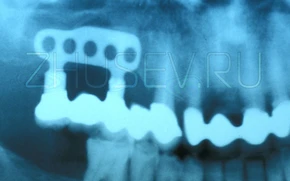

Посмотрите на данный пример. Вид имплантата действительно устрашающий. Это единственный из представленных ниже имплантатов не российская самоделка. Это американский имплантат Ramus Blade. Сразу понятно, что во всем мире путь имплантации был тернист!

Данная конструкция содержит внутренний винт, который при заворачивали раскрывал лепестки в нижней части имплантата. Так, как это бывает с обычным строительным дюбелем.